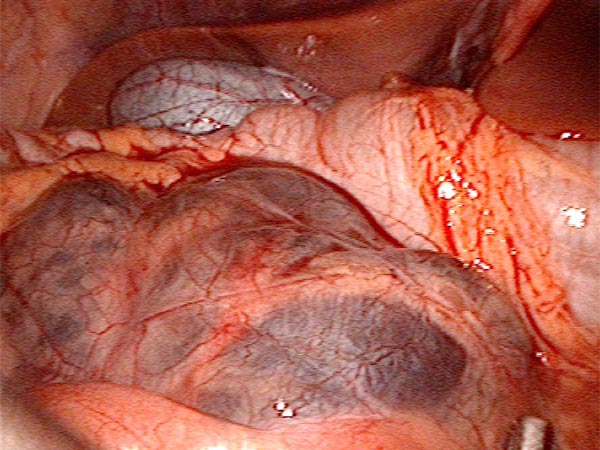

Blick vom Nabel zum rechten Oberbauch mit Leber und Gallenblase. Im Mesenterium des Dünndarms weitere durchscheinende Zysten.

Laparoskopische Resektion von mehr als 90 % der Zysten. Hier Blick auf die von dorsal durch das Peritoneum sichtbaren, retroperitoneal gelegenen Zysten der LM.